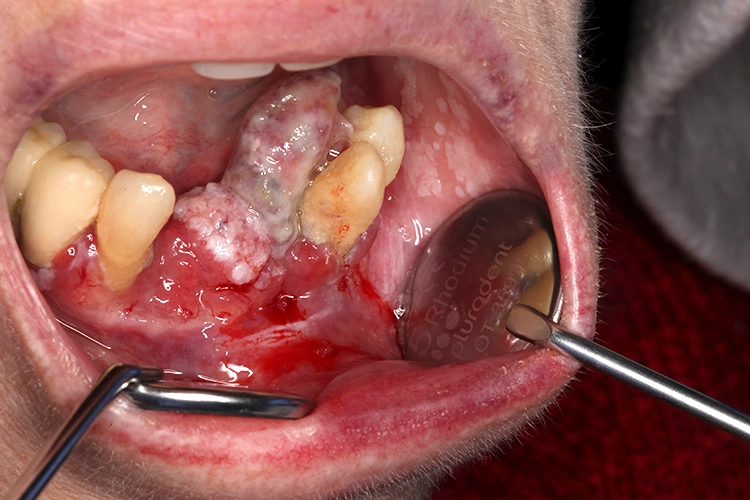

Veränderungen der Mundschleimhaut können vielfältig in Erscheinung treten. Häufig sind es entzündliche Stomatitiden, die sich einfach mit prednisolonhaltiger Salbe behandeln lassen (z.B. Dontisolon®) [2]. Leukoplakien lassen sich dagegen schwerer genau bestimmen. Sie zeigen sich als vornehmlich weiße Läsionen, die weder klinisch noch histologisch einer anderen Mundschleimhautveränderung zugeordnet werden können [3].

Tritt innerhalb von 2 Wochen keine Besserung bzw. Ausheilung der Mundschleimhautveränderung ein, besteht der Verdacht einer Vorläuferläsion, die von einem Spezialisten histologisch auf ihre Dignität hin untersucht werden muss [1,4].